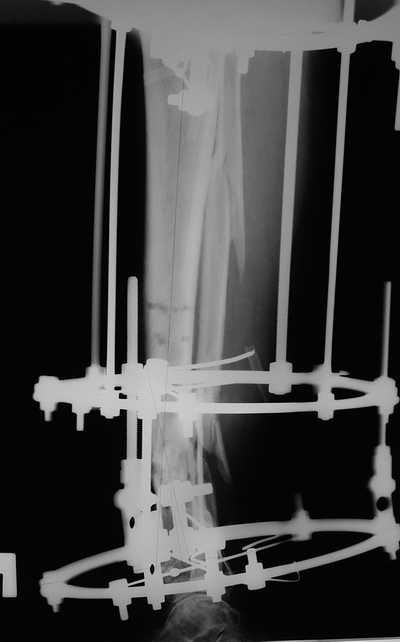

Женщина 46 лет, неудачно лечившаяся по поводу перелома голени в нижней 1\3

сначала в гипсе,  поступила через 6 месяцев после остеосинтеза пластиной

(рис 1). Имелась деформация в нижней 1\3 голени: варус, антекурвация,

наружная ротация, два свища. Удалена пластина, дебридмент мягких тканей,

остеотомия м\б кости, аппарат Илизарова. По рентгенограммам в двух проекциях

произведено планирование устранения смещений (рис 2 и 3), между вторым и

третьим кольцом установлены 6 телескопических дистракторов Гесапода, данные

введены в программу, и далее втечение 10 дней больная подкручивала телескопы

согласно выданной компьютером инструкции. По завершению репозиции

гексаподные телескопы обратно заменены на обычные штанги от аппарата

Илизарова (рис 4 и 5). Еще через две недели забит гвоздь (рис 6, контроль

через 4 месяца).